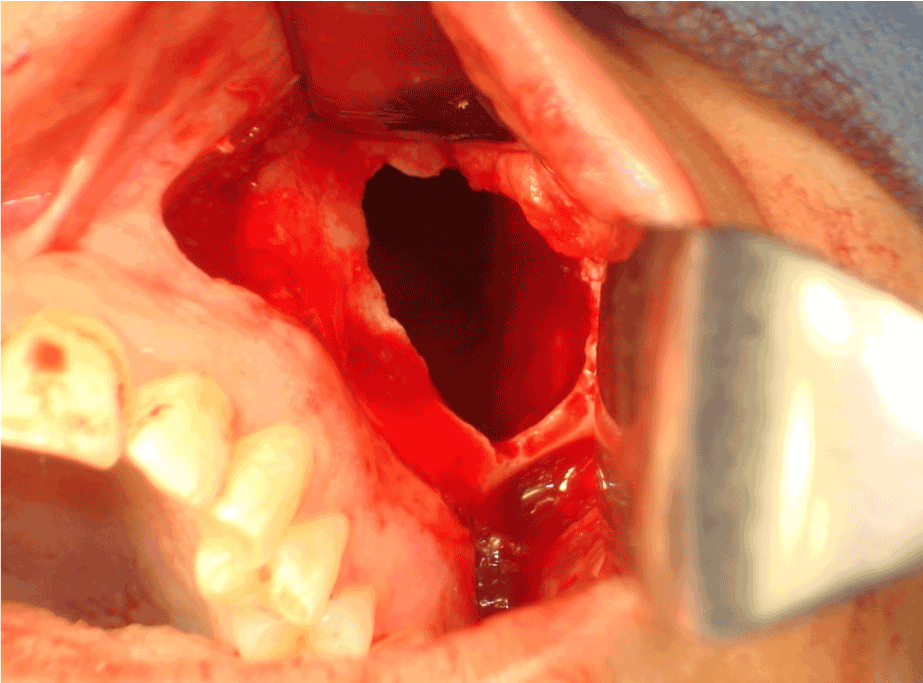

Under general anesthesia, the lesion was enucleated with curettage of the floor of the sinus where the lesion was implanted using rotary instrument through Caldwell Luc approach (Figures 5, 6).

Figure 5. KCOT within left maxillary sinus is exposed through Caldwell Luc approach.

Figure 6. Post-enculation area of the lesion.